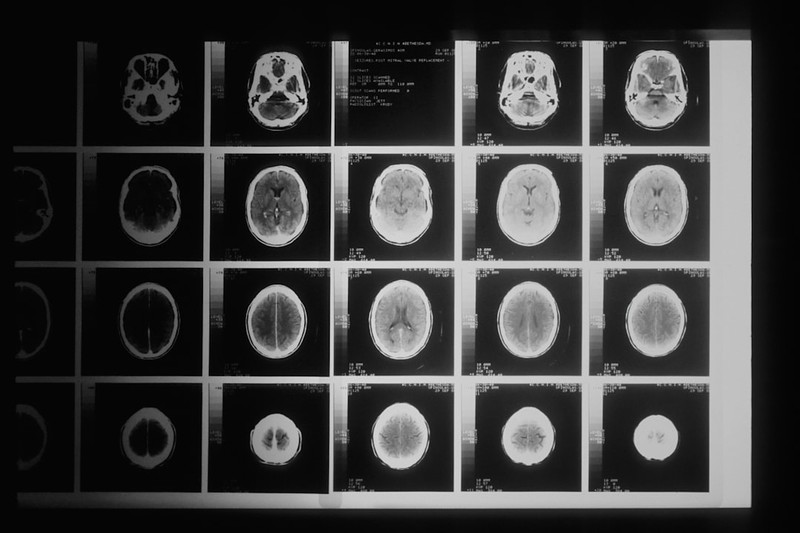

The study’s central finding isn’t just that plastic is in the brain — it’s where it concentrates. Peritumoural tissue, the brain matter directly surrounding tumours, contained significantly higher MNP levels than healthy tissue. The blood-brain barrier near tumours is known to be compromised; the leading explanation is that this breakdown opens a physical door for particles that would otherwise be filtered out.